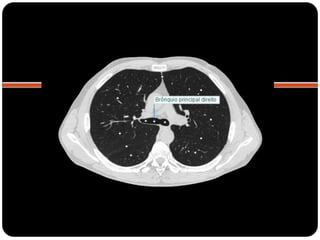

BRÔNQUIOS

PRINCIPAIS

LOBARES

SEGMENTARES

 Brônquios principais originam-se da traquéia

na carina;

 Brônquio direito: ângulo mais obtuso com o

eixo longo da traquéia;

 Direito(2,2cm) mais curto que o

esquerdo(5cm);